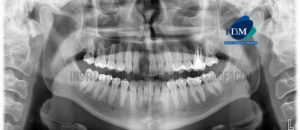

Paciente masculino de 17 años acude al Instituto de Diagnostico maxilofacial para evaluación imagenológica general. A la evaluación de la radiografía panorámica, evidenciamos que las